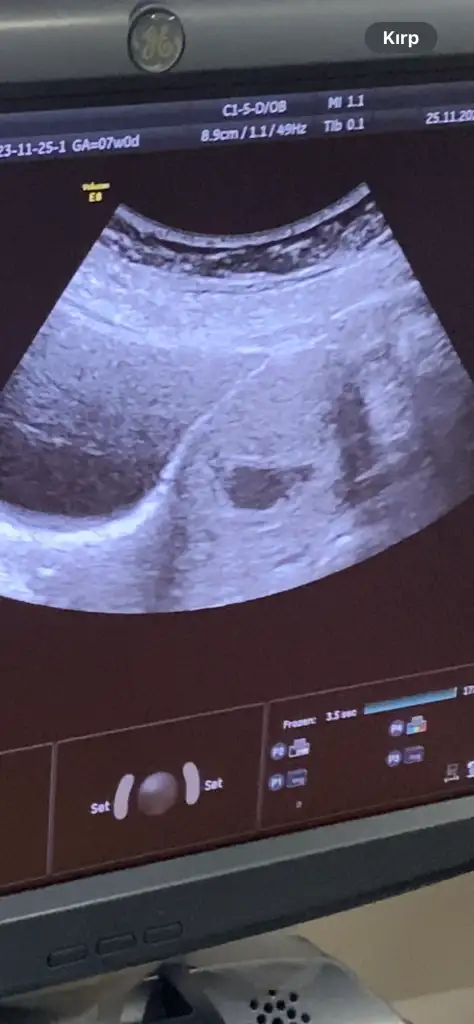

Ben birşey merak ediyorum dun doktora ilk defa gittim karından muayenede goremedı alttan muayenede 5 haftalık dedı ama ultrasyonda boyle kesenın ıcınde bırsey yok bombos duruyor adet tarıhıme gore hesaplama yaptı ama ben 5 haftalık oldugunu sanmıyorum

Ben konuyla alakasız birsey soracam 5 haftalık ama kesenin icinde birşey yok acaba doktor haftayı mı yanlış soyledı burda bakıyorum 6 haftalıklar da kocaman birşy var kesede benim bomboş gorunuyordu

Geç döllenme olabilir belki ya da kişiden kişiye değişir diye düşünüyorum